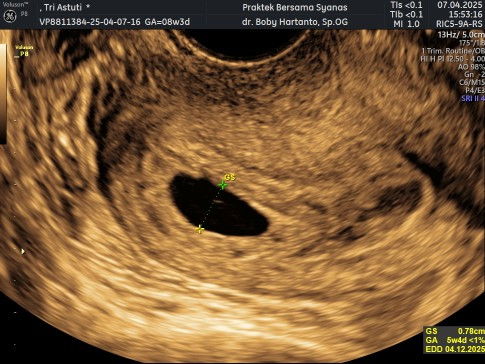

Bunda bunda.. sya kemarin USG diusia kehamilan 8 week lebih 3 hari. Karena tidak terlihat janin nya, jadi saya USG transvaginal juga, tapi tetap tidak terlihat janin nya hanya kantung saja seperti difoto. Apakah masih ada harapan bunda, di 2 kedepan Minggu sudah terlihat janin 🥹🥹 Apa ada yang ngalamin juga?? Sya khawatir terus sambil menunggu USG berikutnya.